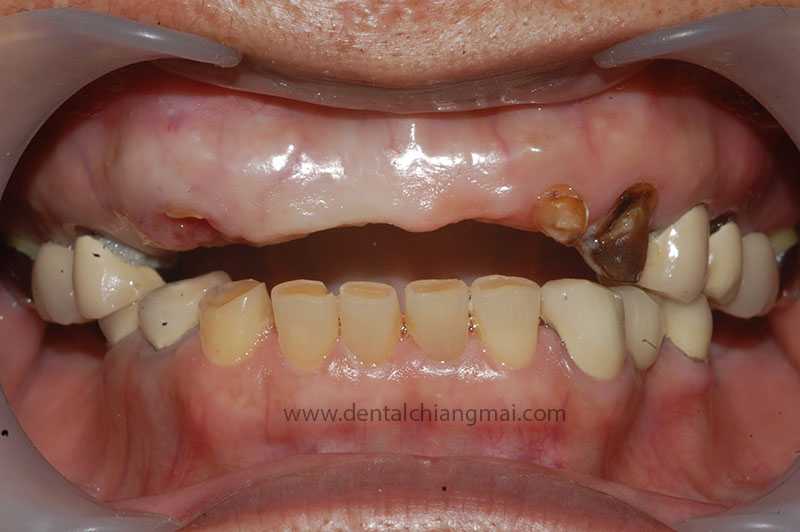

CASE 1 : 5 implants with 3 unit Bridges on upper front maxilla.

Before: